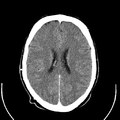

أشعة مقطعية للرأس توضح صورة المخ